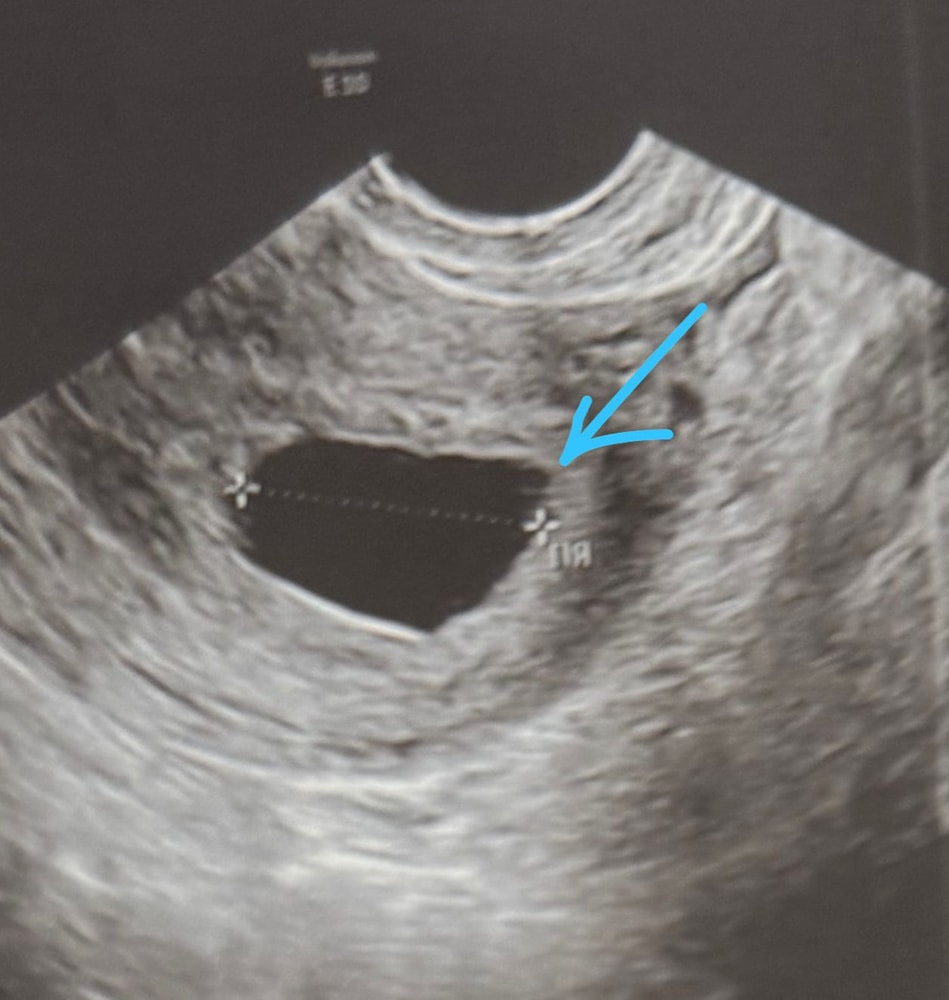

Срок б28.06.2025 сегодня была на узи. Плодное яйцо 21,4мм внутри ничего не увидели. Врач сделала заключение анэмбриония. Мне так кажется или в плодном яйце что-то виднеется?

Это, скорее всего, просто «шумы», при таком плодном яйце уже четко все видно. Но, дай бог🙏🏻

Анна, при анэмбрионии растёт, при каком размере пя у вас исчезло? Я надеюсь на поздную овуляцию, так как цикл у меня не регулярный. У некоторых при пя 23-24 мм эмбрионы только были видны как я читала. Очень надеюсь что нормально всё будет. А на фото узи мне прям видно что то.

Анна, нет не увидели, думаю может то что еле еле заметный это желточный мешок? Не знаю даже, врач сказала на следующей неделе придти на повторное узи. Если тогда ничего не будет, то точно пя пустой

Ксеня,врач 6-7 недель сказала. Сказала придти на повторное узи через неделю.Мне прям виднеется маааленький кружочек, вам видно? Или мне одной так кажется